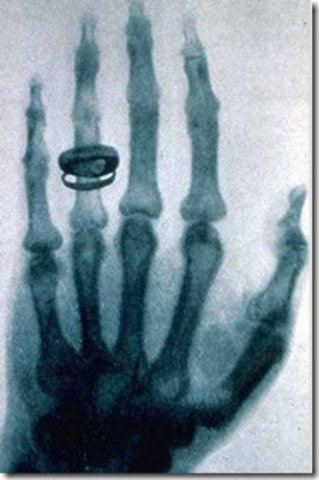

Wilhelm Rontgen : que los rayos influían en la emulsión fotográfica, lo que desencadenó nuevas pruebas. Pronto comprobó que los rayos atravesaban la materia e impresionaban su forma en la fotografía. Al tiempo decidió experimentar con el cuerpo humano. Su esposa expuso su mano a los rayos y la colocó sobre la placa. Obtuvieron así la primera radiografía del cuerpo humano (incluyendo su anillo!), un avance que revolucionaría posteriormente la medicina.